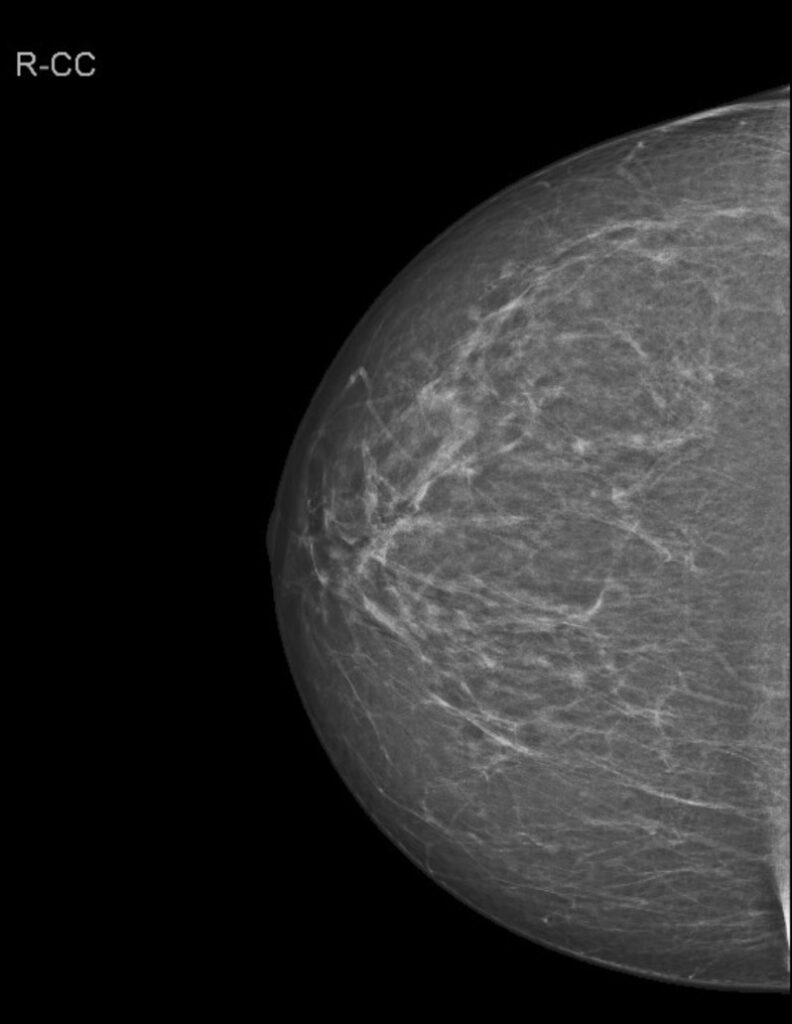

Vorsorgemammographie. Zum Zweitbefunden. Welche BIRADS Einstufung wählen Sie? (Anmerkung: 0 gilt nicht!).

Wenn Sie etwas anderes als 1 wählen, geben Sie die Veränderung mit Seite und Beschreibung gemäß BIRADS an!